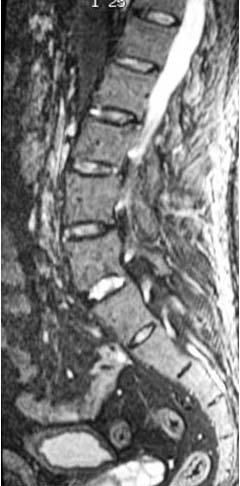

La afectación inflamatoria se manifestó, en todos los casos, como hiperintensidad en secuencia STIR y captación de contraste en secuencias T1. Doce pacientes presentaron afectación inflamatoria en la columna, ASI o caderas (figs. 1, 2 y 3).

Fig. 1.--Diferentes grados de afectación inflamatoria en cuerpos vertebrales. Secuencias STIR y SE T1 con contraste paramagnético.